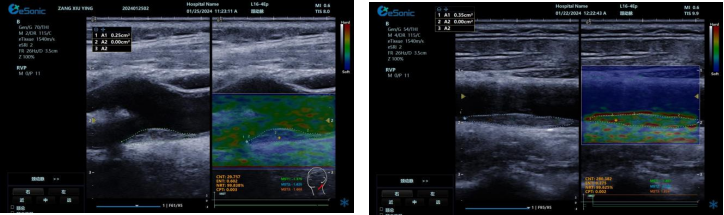

RawVisionTM Plaque技术(RVP

RVP 是世界领先的颈动脉斑块自动定量分析成像模式,依托 RawVisionTM原数平台强大的原始射频数据采集与分析能力。其优势显著:

? 可视化呈现方面,能分析斑块在特定条件下内部纹理变化,生成可视化参数成像。医生可依据颜色辨别易损与稳定斑块,并进行定量测量。

image.png

? 定量评估上,提供 CNTENTNRTCPT 等指标和参数,为监测老年颈动脉斑块风险提供客观准确依据。

? 借助 AI 自动分析,可快速筛选诊断,提升脑卒中筛查效率,有望重塑易损斑块临床诊断流程。

? 具备技术升级潜力,支持高端科研,能挖掘更多诊断参数,满足临床需求。

相比传统超声弹性成像技术,RVP 利用颈动脉搏动采集数据,避免了操作者施压等主观因素干扰,数据处理更精准,结果重复性佳,不受操作者差异影响。